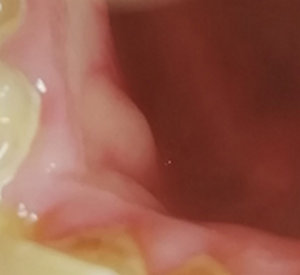

Подскажите, пожалуйста. Болела десна около недели, незначительно. Позже образовался какой-то шарик, похожий на прыщик. А после, во время еды что-то стало мешать и вот появилось непонятное новообразование из десны. На ощупь твердое, беспокоит во время приема пищи.

Очень сложно определить, но все Ваши симптомы говорят и свищевом выходе. То есть, на верхушках зуба имеется воспалительный процесс.